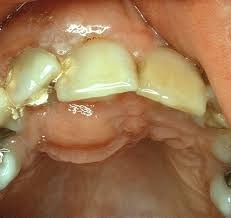

Acute Apical Periodontitis is an inflammation of the periapical tissue located at the apex of a tooth root, usually caused by bacterial infection from untreated dental caries, trauma, or failed dental procedures. The condition can progress rapidly, causing severe pain, swelling, and sensitivity to pressure. If left untreated, it may lead to abscess formation, systemic infection, or tooth loss.

Dental professionals often detect Acute Apical Periodontitis through clinical examination and radiographic imaging. Early detection is key, as timely intervention can prevent further complications and preserve dental structure.

Diagnosis and Examination

Dentists rely on a combination of clinical evaluation and radiographic imaging to diagnose Acute Apical Periodontitis. The process typically involves:

1. Visual and tactile examination: Checking for swelling, gum tenderness, or abscess formation.

2. Percussion tests: Gently tapping the tooth to assess sensitivity and inflammation.

3. X-rays: Identifying bone loss, root tip inflammation, or infection spread.

4. Pulp vitality tests: Determining if the tooth pulp is still alive or necrotic.

Accurate diagnosis allows for precise treatment planning and better patient outcomes.